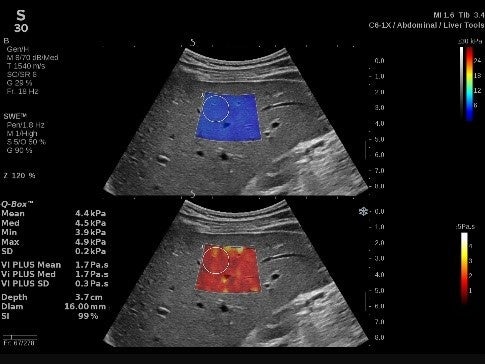

(2)進化したSWE PLUS™イメージング

従来システムではSWEのレンジは800 kPaまででしたが、SUPERSONIC™ MACHシリーズでは、最大1200 kPaまで測定が可能*となっています。

*MSKプリセット使用時

整形領域では腱や筋肉の硬さ、乳腺領域では腫瘍の硬さ、肝臓領域では、肝組織の硬さを評価することで、疾患の早期診断に貢献します。

(3)新たに搭載したVi PLUS™イメージング

肝臓組織の粘性の定量化、弾性率のリアルタイム表示、剪断弾性波伝搬速度のディスパージョン評価を可能*にするモードです。

*C6-1Xプローブ、Liver & Abdomenプリセット、Generalプリセット使用時SWE PLUS™イメージングとVi PLUS™イメージングは同時リアルタイムに表示されます。